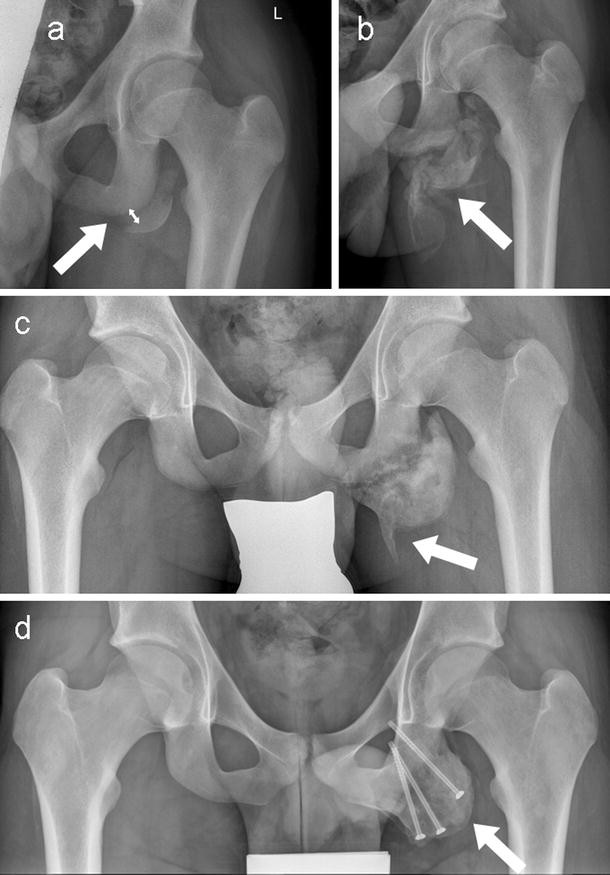

Pelvic avulsion fractures are usually caused by activities or sports that need speed and sudden stops. Though more common in children, athletic adults are also prone to avulsion fractures. Other sites in the upper extremity involve the humerus and include the greater and. A pelvic avulsion fracture is where the tendon comes away from the bone, often taking a piece of bone with it. Avulsion fractures are caused by trauma. Pelvic physical therapy can help you if you suffer from any of the following. They include pelvic ring fractures [significance of physical examination and radiography of the pelvis during treatment in the shock. In adults, the ligaments and tendons tend to be injured first, whereas in children the bone may fail before. Apophyseal avulsion fractures are usually the result of a sudden forceful concentric or eccentric contraction of the muscle attached to the apophysis. Physical exam should not be used to rule out a pelvic fracture in unconscious patients, but it can nearly definitively rule it in. They usually happen when a bone is moving one way, and a tendon or ligament is suddenly pulled the opposite way. Patients and families need to be counseled about this. Many hip fractures can be treated with physical therapy, rest, or injections.

A pelvic fracture is a disruption of the bony structures of the pelvis. Avulsion fractures are most common in the pelvis. Detailed explanation of pelvis avulsion fracture or avulsion fracture of the pelvis. Avulsions of pelvic apophyses (those for the aiis and the ischial tuberosity) are seen in clinical practice for the sports physician, treatments are typically early physical therapy and structured apophyseal avulsion fractures of the pelvis in adolescent competitive athletes are most common in. Pelvic floor physical therapy plays a key role in calming and desensitizing the central nervous system, and as such, it is considered the gold standard treatment. In this series, nearly all pelvic avulsion fractures (97%) were managed successfully with a conservative approach. The hip, elbow and ankle are the most common locations for avulsion fractures in the young athlete. Falguni vashi pt, dpt, prpc founder of pelvicure physical therapy. An avulsion fracture is an injury to the bone in a location where a tendon or ligament attaches to the bone. An avulsion fracture occurs when a tendon or ligament attached to a bone pulls against it and fractures off a piece of the bone. Physical therapy can also help improve strength and decrease your risk for loss of function. Patients and families need to be counseled about this. Your doctor might recommend that you use crutches to keep weight off the hip while it heals.

Physical exam should not be used to rule out a pelvic fracture in unconscious patients, but it can nearly definitively rule it in. Severe pelvic fractures can be fatal due to internal bleeding or damage to nearby organs, or result in chronic pain and physical disabilities. Exercise increases blood flow, which delivers more. They are not associated with avulsion fractures or stress fractures. Apophyseal avulsion fractures are usually the result of a sudden forceful concentric or eccentric contraction of the muscle attached to the apophysis. Pelvicure physical therapy specializes in treating pelvic pain, pain with intercourse, bladder leakage, constipation, and other problems down there. Like other pediatric fractures, apophyseal avulsion fractures fail through the physis.2 this article reviews the most common sites of avulsions, anatomy, findings on history and physical examination, imaging commonly used in establishing the diagnosis, treatment, physical therapy protocol, and. Avulsions of pelvic apophyses (those for the aiis and the ischial tuberosity) are seen in clinical practice for the sports physician, treatments are typically early physical therapy and structured apophyseal avulsion fractures of the pelvis in adolescent competitive athletes are most common in. Most often, this occurs during sudden movements and changes in direction. In the pelvis, the newly formed secondary centers of ossification, the apophyses, are the most likely portions of the bone to avulse. Aiis and ischial tuberosity fractures are at increased risk of developing future pain and nonunions, respectively. Pelvic fracture is a disruption of the bony structures of the pelvis, including pelvic ring fractures, acetabular fractures, and avulsion fractures. Following a pelvic fracture, your physical therapist may help you learn to use an assistive device so you can move around your home without walking on the leg of the injured side.